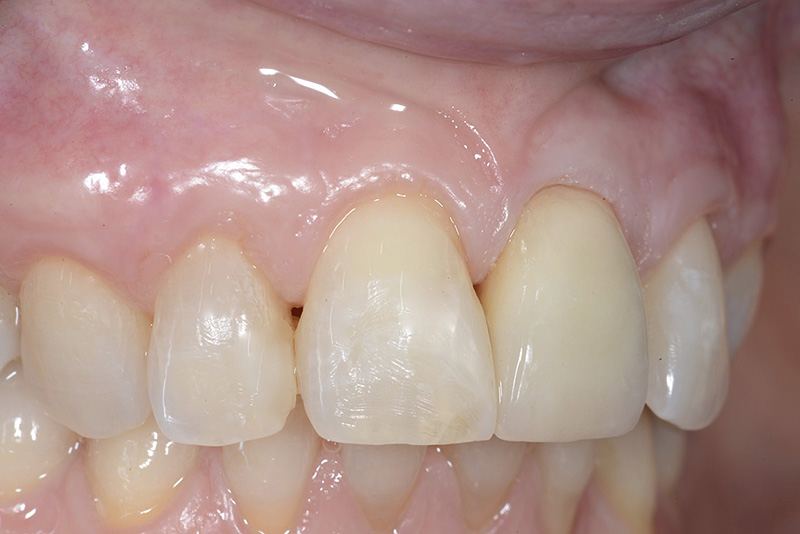

PREMESSA: in seguito all’estrazione dell’incisivo laterale superiore di destra, resasi necessaria per cause batteriche, si decide di affrontare il caso con il posizionamento di un impianto in sostituzione dell’elemento mancante dopo guarigione del sito infetto. Con tecniche rigenerative sia dei tessuti ossei mancanti a causa dell’infezione pregressa, sia dei tessuti gengivali che appaiono inizialmente troppo spostati in alto, si ripristina una corretta morfologia delle parabole (contorni) gengivali e delle papille interdentali (triangoli di gengiva tra due denti vicini).

Vengono utilizzati 2 tipi di provvisori: il primo, cementato ai denti vicini, viene utilizzato dal momento dell’estrazione del dente fino ad impianto osteointegrato (circa 6 mesi); il secondo, avvitato direttamente all’impianto, ha una funzione di prova estetica ma soprattutto di guida per la maturazione dei tessuti gengivali peri-implantari portandoli verso la maturazione completa prima di posizionare la corona finale in disilicato di litio.